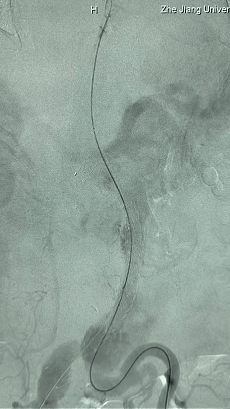

1. 患者平卧位,麻醉成功后,留置导尿,常规术野消毒铺巾。左侧肘部切开,暴露左侧肱动脉,置入6F鞘。双侧股动脉穿刺,分别置入10F鞘,全身肝素化。

2. 左侧肱动脉入路,超选至降主动脉,更换8F-900mm长鞘,造影提示IV型胸腹主动脉瘤,累及双肾动脉。